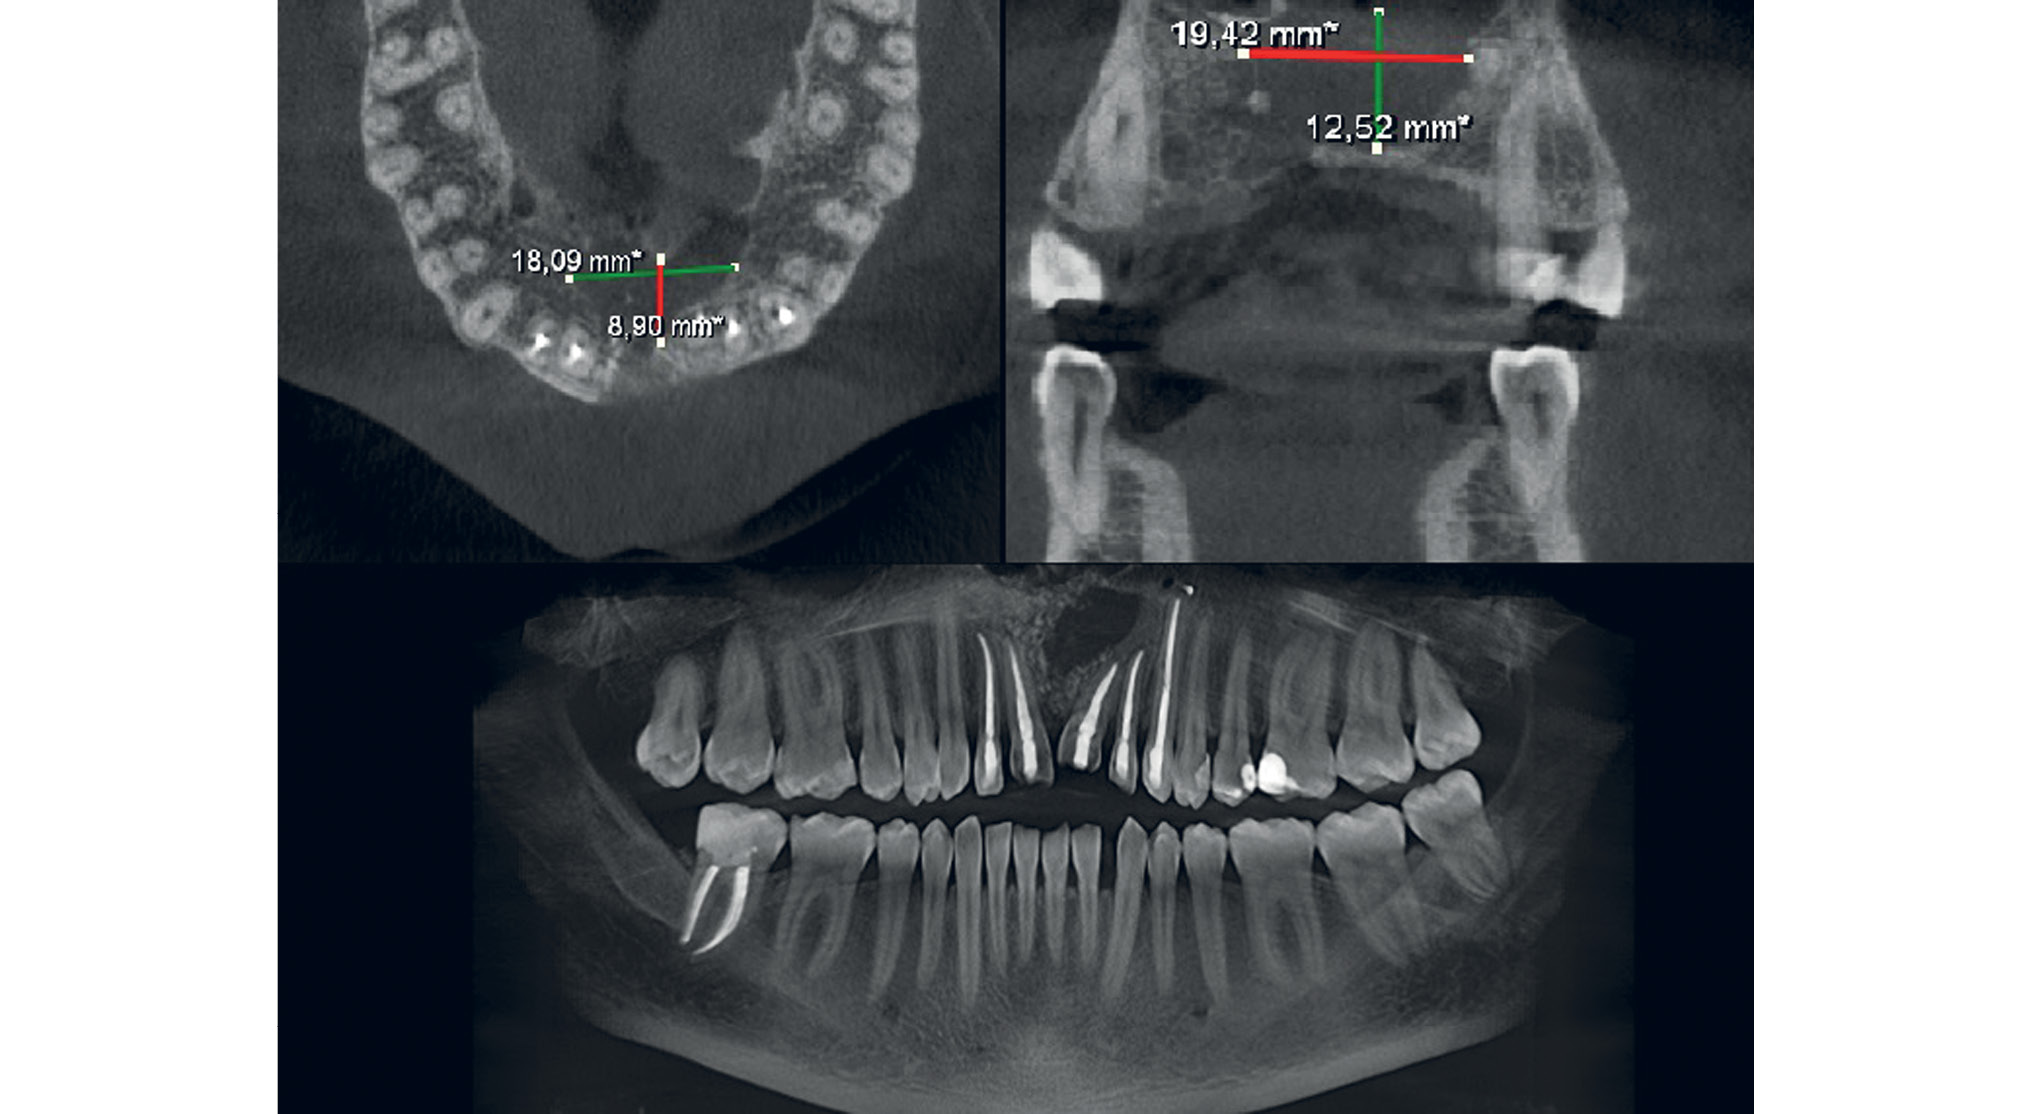

На контрольном осмотре на 30-е сут после оперативного вмешательства больной жалоб не предъявлял. В области послеоперационного рубца слизистая оболочка бледно-розового цвета. Дефектов слизистой оболочки нет. Пациент отмечает улучшение носового дыхания. По данным контрольной конусно-лучевой компьютерной томографии полость кисты заполнена однородным содержимым. В области кортикальной пластинки верхней челюсти равномерно распределен ксеногенный костнозамещающий материал (рис. 3).

Рис. 3. Пациент Д., 33 года: данные контрольной конусно-лучевой компьютерной томографии через 1 мес после операции. Полость кисты заполнена однородным содержимым, дефект передней стенки верхней челюсти слева замещен пластинчатой титановой сеткой

На протяжении последующих 7 мес пациент 1 раз в неделю приходил на перевязку для замены йодоформной турунды. Клинически из раны выделялось содержимое слизисто-серозного характера. За время проведения перевязок размеры дефекта уменьшились примерно в 2 раза (рис. 4).

Рис. 4. Пациент Д., 33 года: контроль конусно-лучевой компьютерной томографии спустя 7 мес после операции